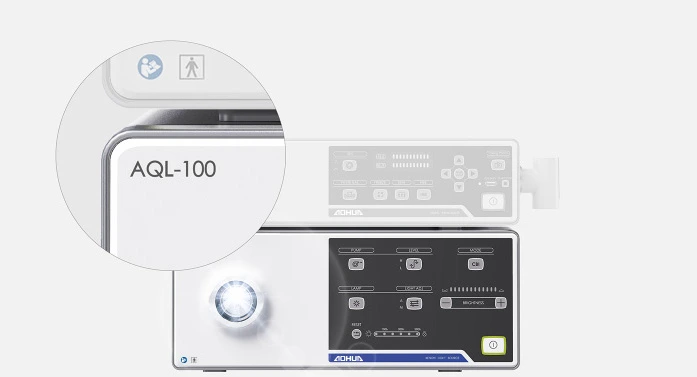

Видеоэндоскопическая система на базе Aohua AQ-110

Видеоэндоскопическая система Aohua AQ-110 Full HD - это отличная визуализация и потрясающий функционал. Данная видеоэндоскопическая система создана на основе видеопроцессора Aohua AQ-110.

Видеоэндоскопическая система Aohua AQ-110 предлагает вам широкий выбор эндоскопов и функций, а также улучшенное разрешение формата Full HD. Совместима с диагностическими и терапевтическими эндоскопами для ЖКТ, видеобронхоскопами и видеоларингооскопами.